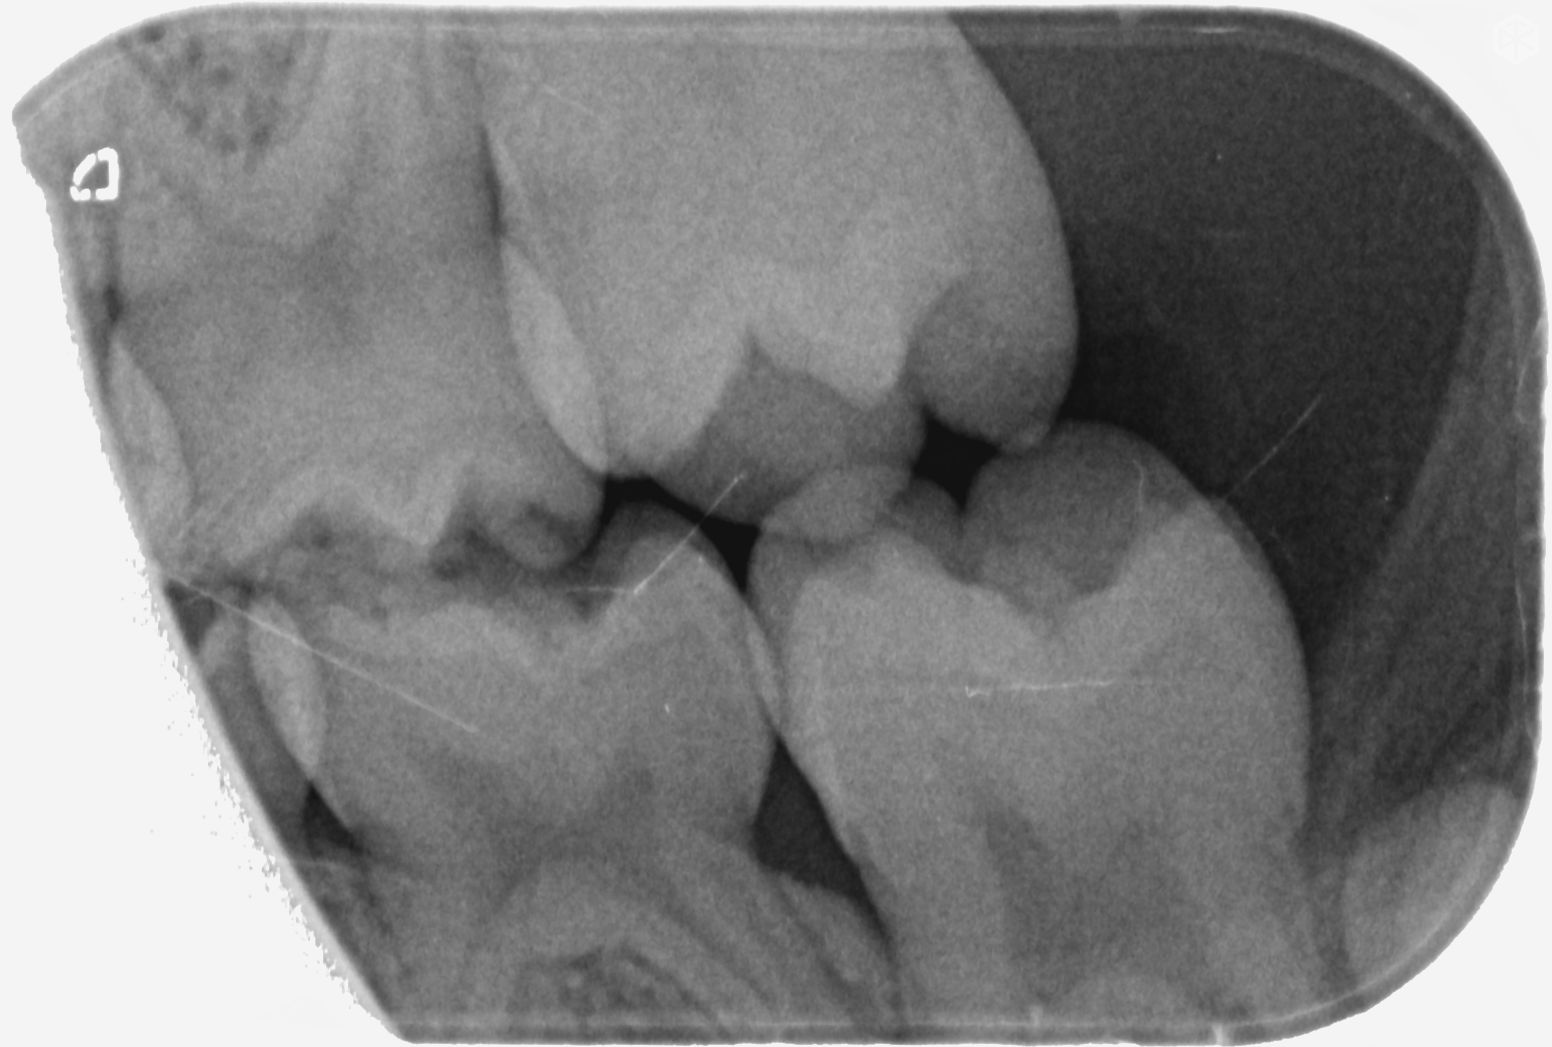

Bijgevoegd 2 XR-beelden van de melktand kiezen van onze dochter van 6. Bij een controle bij onze tandarts werden haar tanden visueel gaaf bevonden, maar wou men toch graag een foto maken. Hierop ziet de tandarts 6 gaatjes die ze in 3 sessies wil open maken en vullen. Uiteraard willen wij dat de gaatjes behandeld worden indien nodig. Echter doordat we het gevoel hebben dat er bij elk van ons steeds meerdere problemen gevonden worden waar we geen hinder van ondervinden, zou ik graag een tweede opinie vragen. Omdat ik zelf de beelden niet kan interpreteren, mijn vraag dus of er effectief 6 gaatjes te zien zijn en of het vullen hiervan aanbevolen is. Alvast bedankt voor uw hulp!

De XR beelden

Ik zie mogelijk een gaatje in de 55 en 54. Mogelijk omdat er een overprojectie is. Maar dusdanig klein dat ik zou afwachten tot uw dochter wat ouder is. Na een jaar een vergelijking foto. Maar ik zie geen zes op deze foto's.